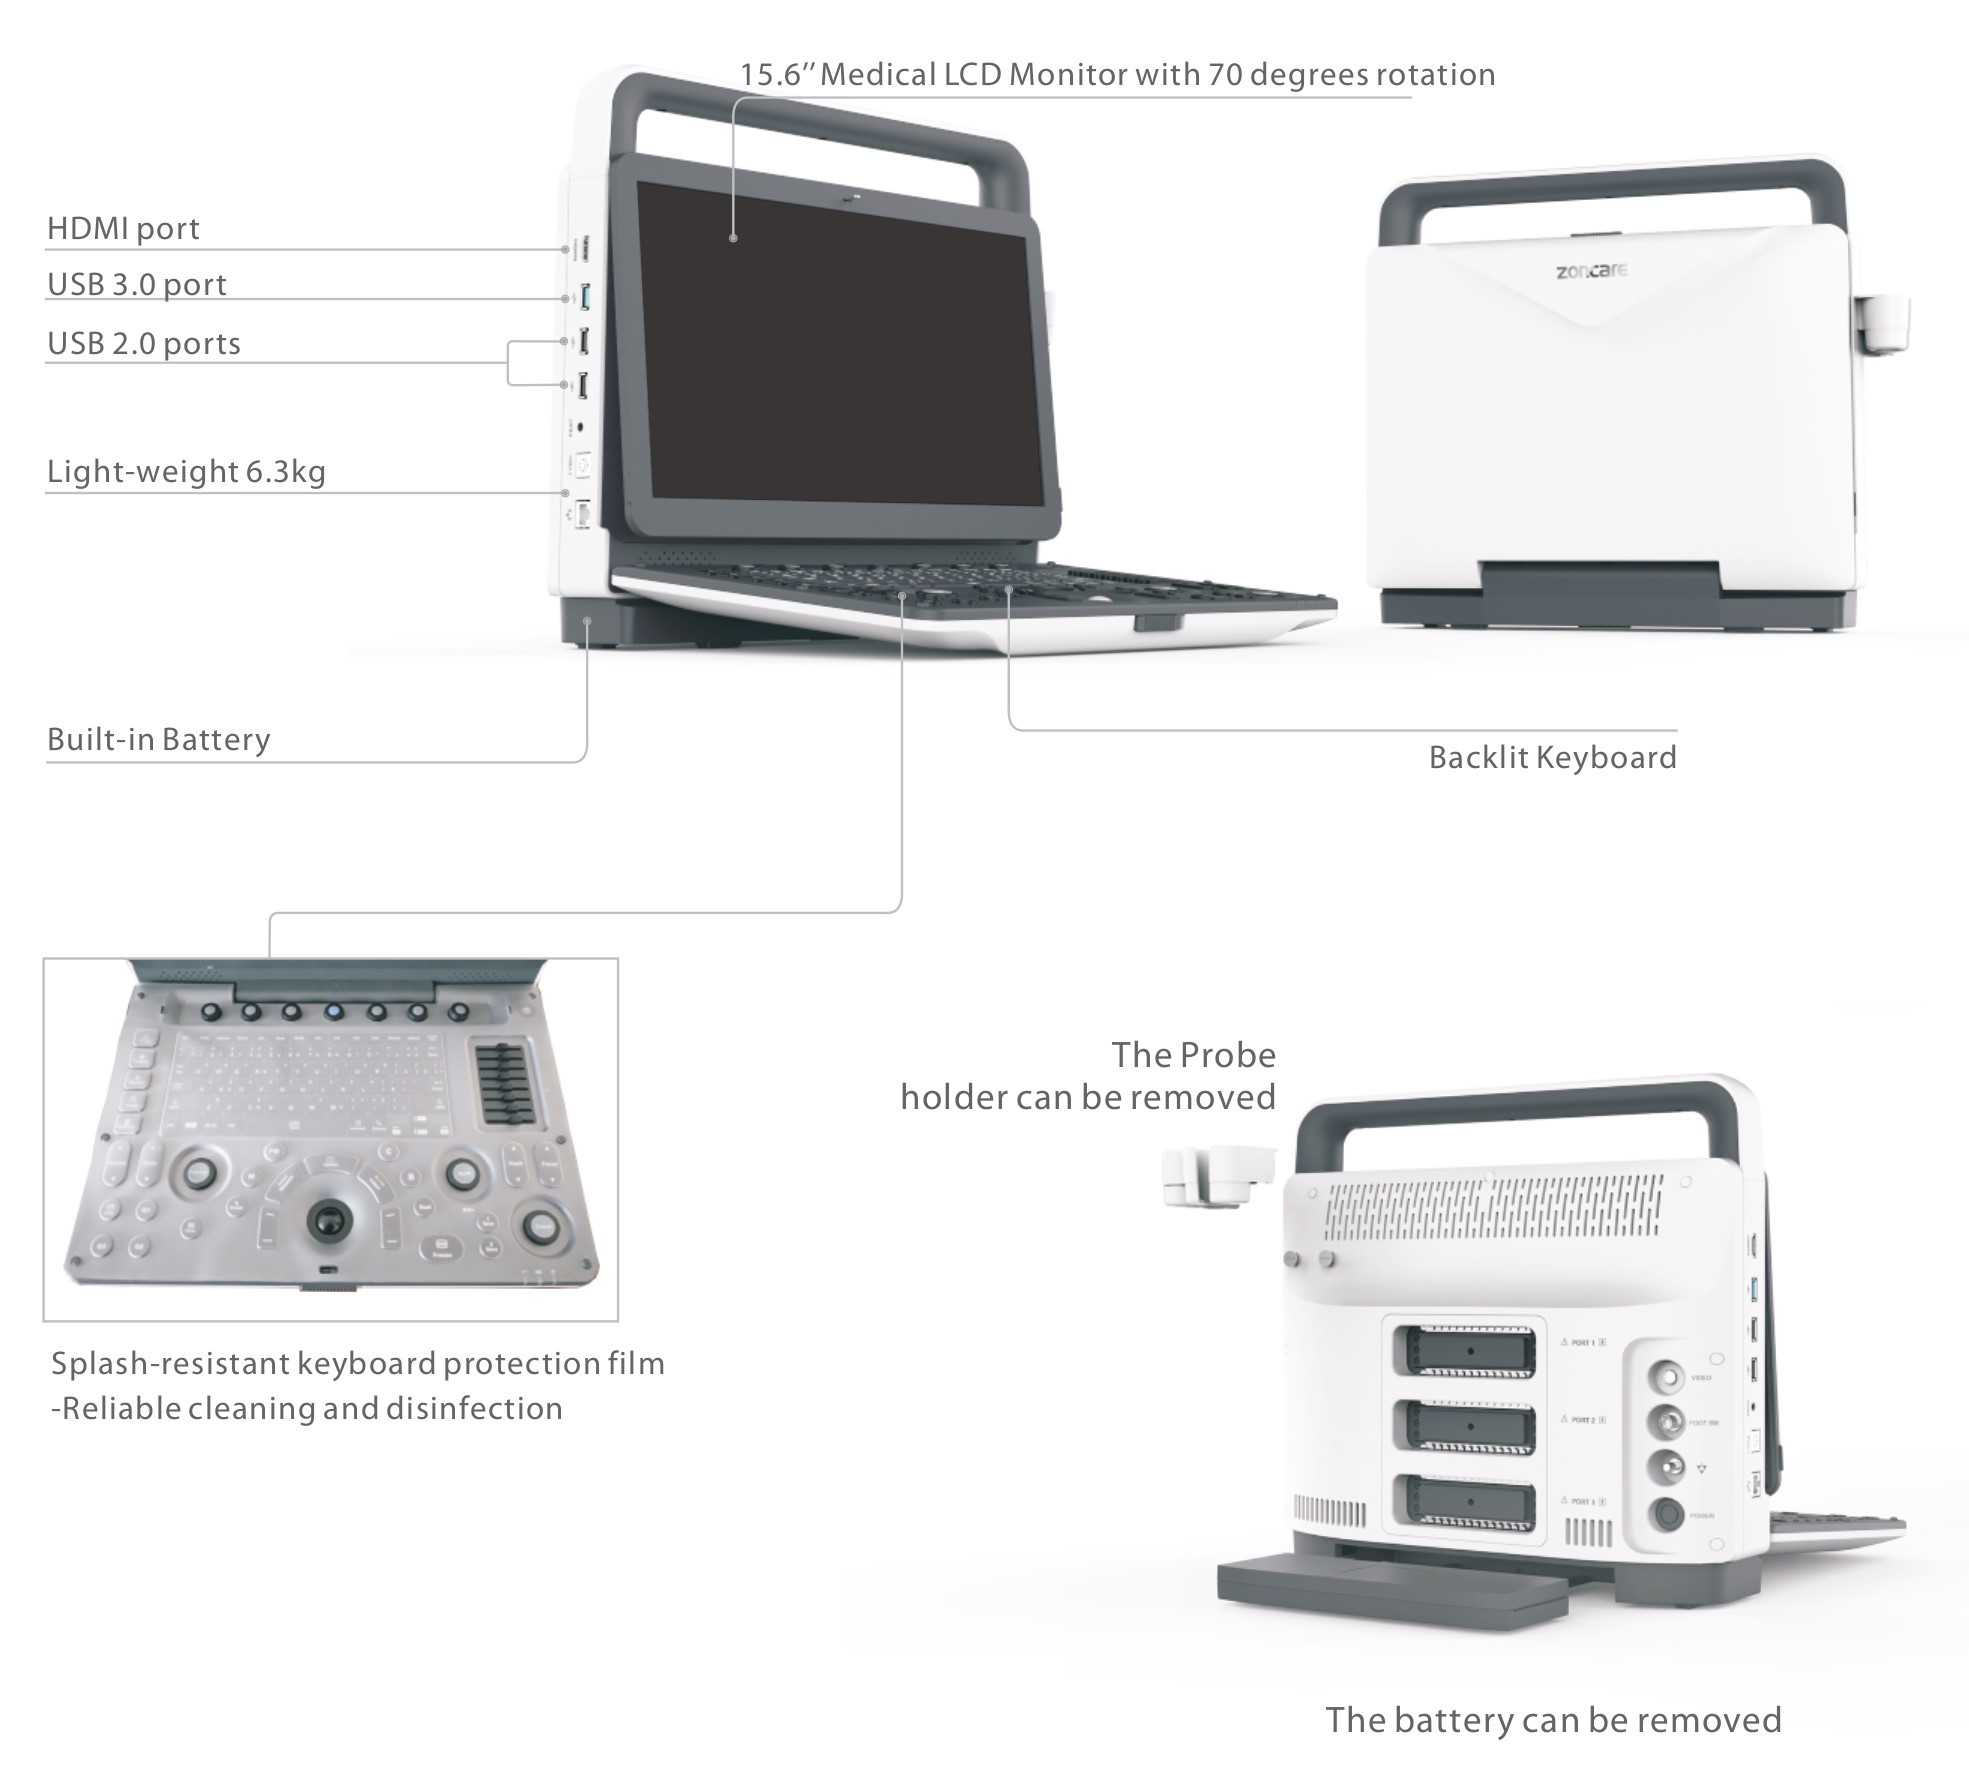

Pantalla y Operación

-

Monitor 15,6” Full HD (1920×1080)

-

Inclinación 0–75°

-

Panel ergonómico con trackball, TGC de 8 segmentos y teclas programables (Q1–Q4)

-

Arranque rápido ~75 s / Apagado ~10 s

Especificaciones Físicas

-

Dimensiones: 380 × 361,5 × 157,2 mm

-

Peso: aprox. 6,45 kg (sin batería)

-

Puertos de sonda: 3 (activados)

-

Alimentación: 100–240 V / 50–60 Hz / 150 VA

-

Batería: 14,4 V / 6500 mAh

-

Sistema operativo: Linux